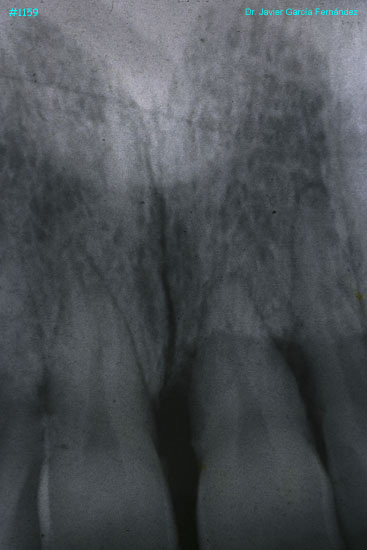

Atlas of Surgical Techniques in Periodontics. Chapter III. Atlas de Técnicas Quirúrgicas en Periodoncia